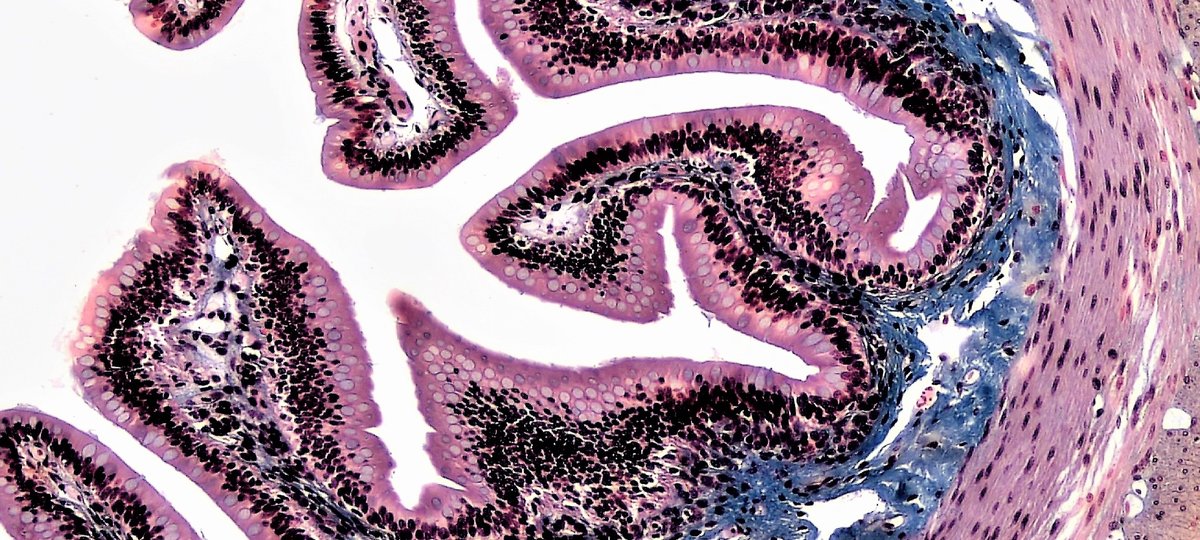

Microscope image of epithelial tissues